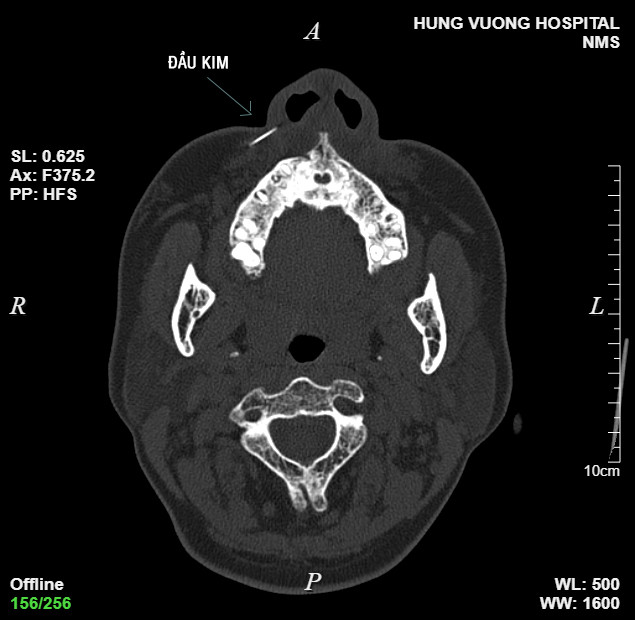

Sau khi thực hiện chụp CT, kết quả cho thấy hình ảnh dị vật khoảng 1cm vị trí phần mềm cánh mũi phải. “Vị trí kim găm sâu vào má, bệnh nhân được bác sĩ chỉ định thủ thuật lấy dị vật”. Sau 10 phút, dị vật là đầu kim đã lấy ra từ vùng má bệnh nhân.